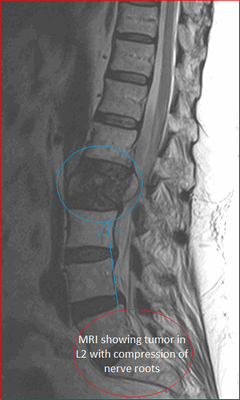

Кроме операций на костных структурах, сегодня с успехом проводится вертебропластика гемангиомы позвоночника. Гемангиома представляет собой сосудистое доброкачественное образование, локализованное внутри костного тела позвонка. Чаще она обнаруживается случайно в ходе МРТ-диагностики, причем излюбленными местами локализации выступают грудной и поясничный отделы. Она обычно охватывает только один из позвонков и при маленьких размерах и отсутствии роста опухоли кавернозного или капиллярного типов не требуют лечения, а лишь регулярного наблюдения.

Пункционная вертебропластика при гемангиоме позвоночника назначается только при ее больших размерах (когда она занимает больше 50% тела позвонка) или агрессивном росте, когда уже присутствует или возникает существенный риск разрушения костной ткани позвонков или наблюдаются сильные боли, провоцируемые сдавлением сосудистой опухолью нервных корешков.

Технически вертебропластика гемангиомы позвонка выполняется так же, как и при переломе позвоночника. Цемент на основе полиметилметакрилата вводится через пункционную иглу в полость новообразования. Поскольку вещество оказывает цитотоксический и термический эффект на нервные окончания, в результате наблюдается устранение болевого синдрома. Дополнительно цитотоксические свойства препарата способствуют прекращению образования новых и роста существующих клеток гемангиомы, что приводит к регрессу опухоли.